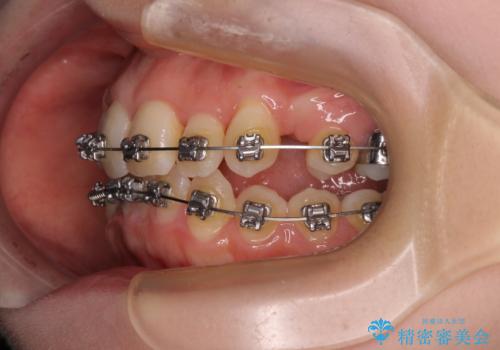

- 矯正装置

- メタルブラケット

- 治療計画

- 八重歯が気になるとのことで来院された患者様です。

上顎前歯部はデコボコが強く、歯を並べるためのスペースが不足しているため、左右の第一小臼歯を抜歯することとしました。

また、抜歯して確保したスペースが不足してしまうのを防ぐため、補助装置を併用しています。

矯正治療の前に上下左右の親知らずの抜歯も行いました。